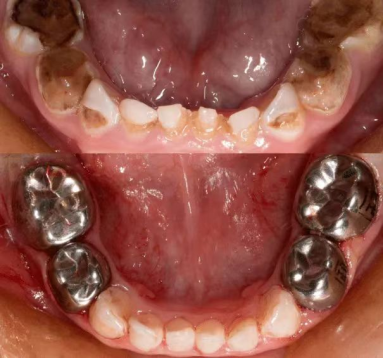

乳牙金属预成冠

这是一种预制成型的,具有乳磨牙牙冠形态的不锈钢金属冠,通常用于恢复乳牙形态和咀嚼功能。金属预成冠套在乳牙上可以保护牙齿并加强牙齿的强度,能够确保乳牙正常健康地被恒牙替换。